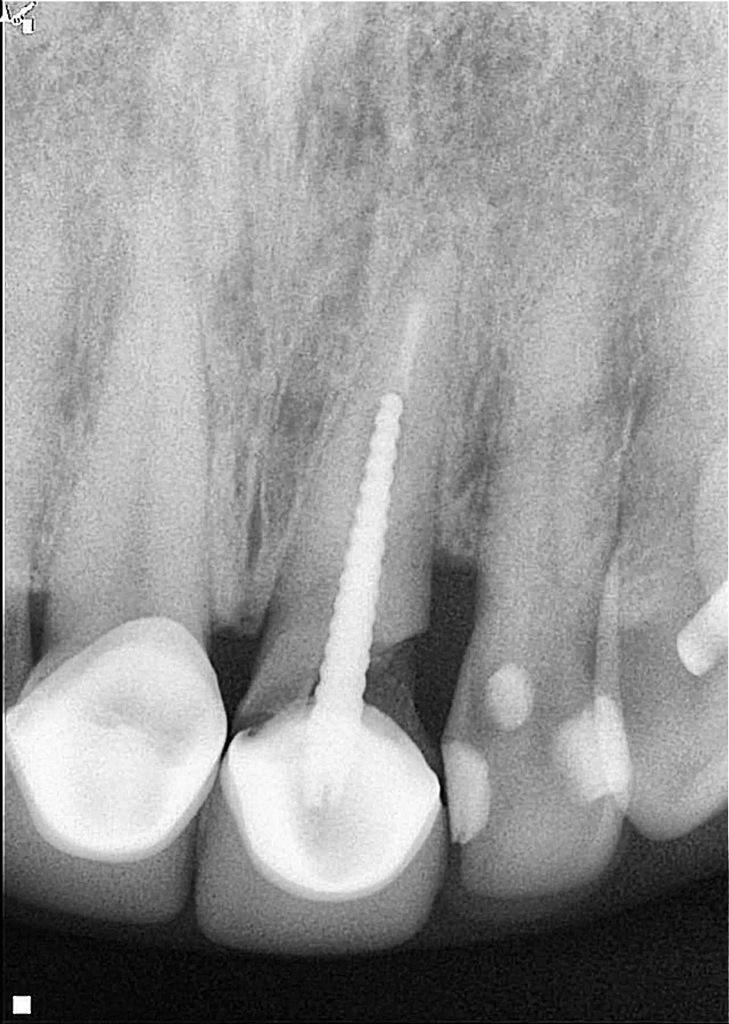

Рентгенологическое исследование, проведенное через два года после экструзии, выявило хорошее периапикальное заживление и продолжающийся вертикальный рост кости на межзубном гребне, главным образом в дистальной области (фото 5). Сообщалось, что нормальный контур периодонтальной связки может наблюдаться через три месяца после операции, а периапикальное восстановление и восстановление рентгенопрозрачности обычно наблюдаются через шесть месяцев, а также минимальная потеря костной массы, часто связанная с повреждением кости в процессе экструзии. Через два года наблюдалось полное восстановление периапикальной ткани и продолжающееся ремоделирование кости, главным образом в области дистального гребня (фото 6). Зуб остается бессимптомным, немобильным и полностью функциональным с эстетической и биологической точек зрения (фото 7). Рентгенологическая картина после четырехлетнего периода наблюдения показала стабильные результаты (фото 8).

Фото 8: После четырехлетнего наблюдения периапикальная рентгенограмма показала отсутствие признаков воспаления в периапикальной области, отсутствие признаков резорбции корня, увеличение костной массы в области дистального гребня и нормальное состояние периодонтальной связки.